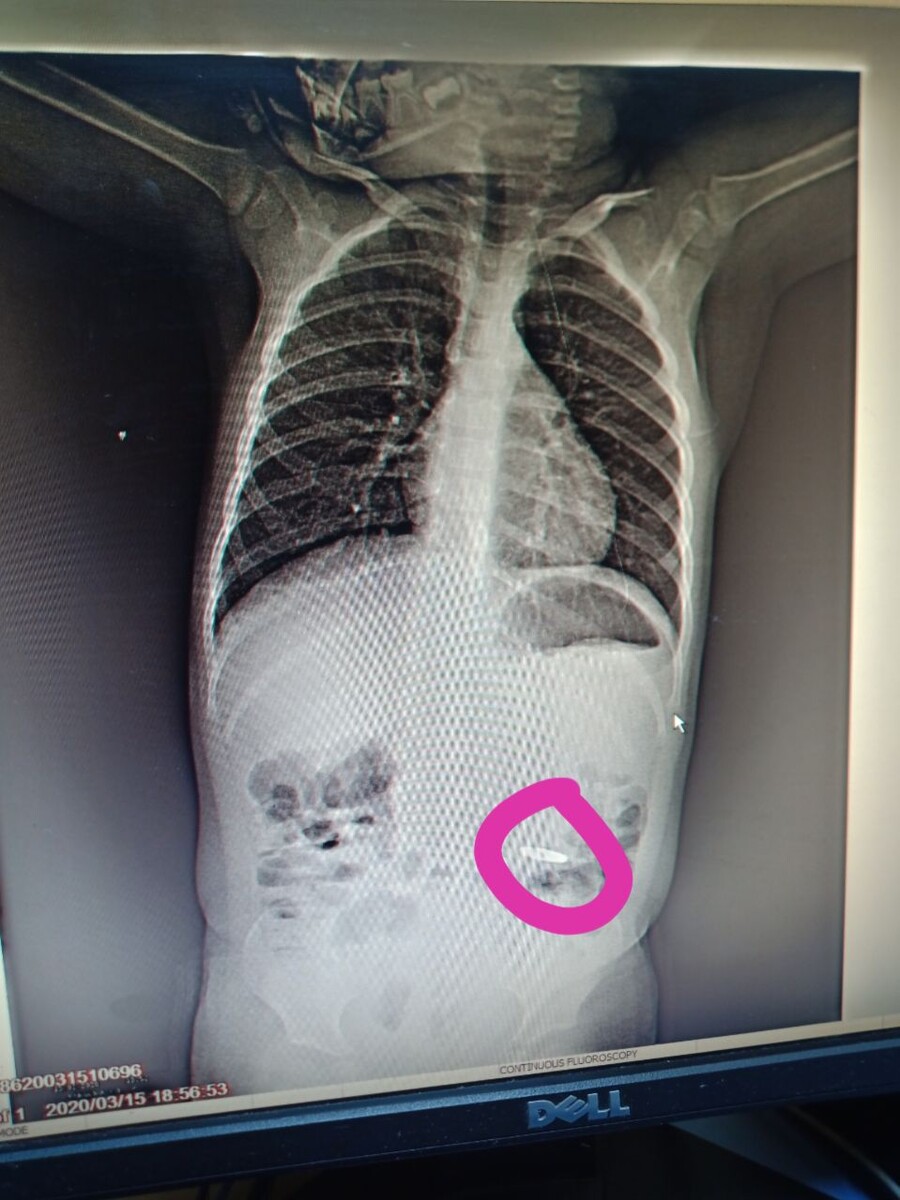

Ребёнок, 2,5 года, проглотил монету (2 рубля). Извлекли эндоскопом)))